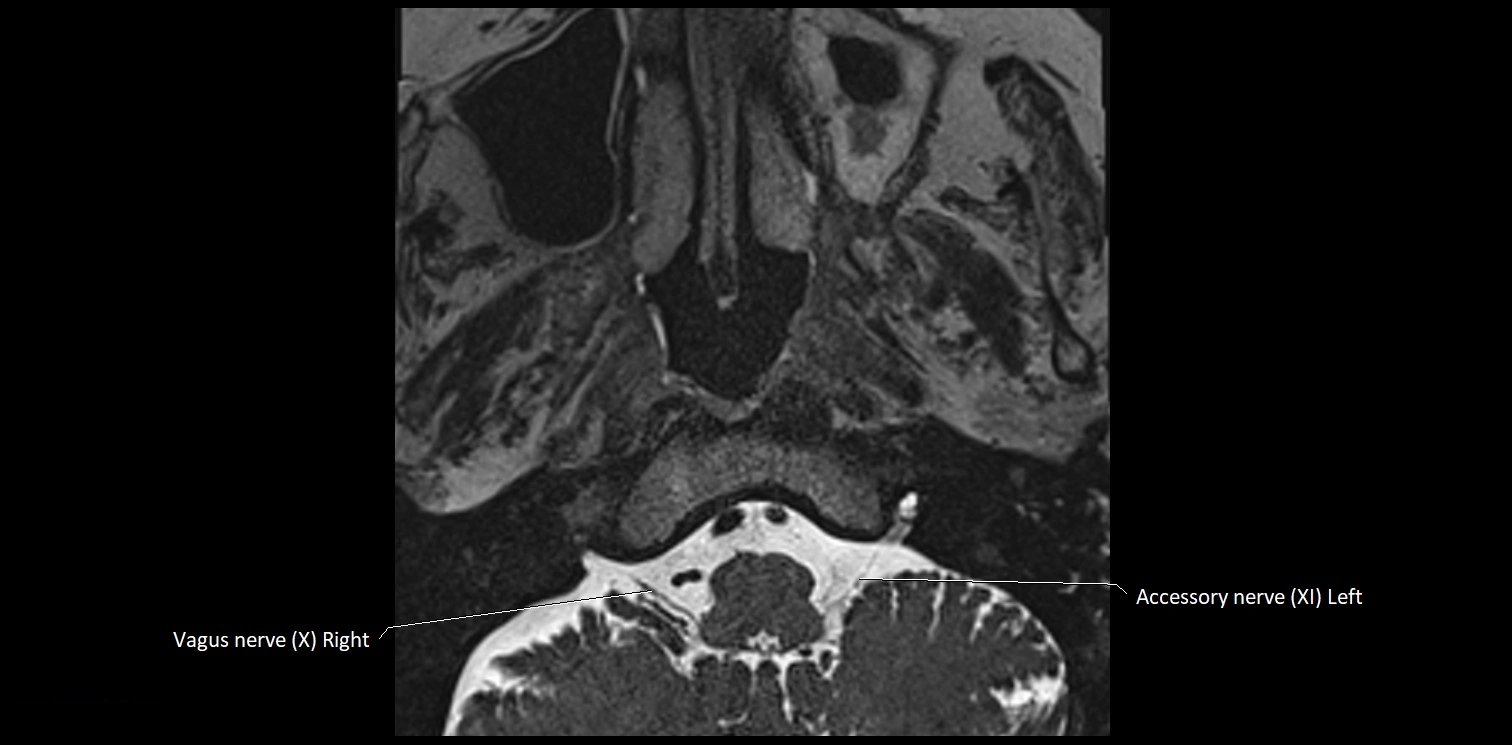

MRI images

image